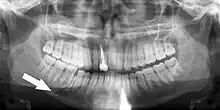

Panoramic radiographs have the capability to demonstrate a portion of the neck and display atheromas (calcifications in the carotid artery) which are an indication of both local and generalized (systemic) atherosclerosis. Atherosclerosis of the coronary arteries leading to myocardial infarction (heart attack), and atherosclerosis of the carotid artery leading to stroke are the number one and number three most common causes of death in the United States.[6]

There is interest to look at panoramic radiographs as a screening tool, however further data is needed with regards if it is able to make a meaningful difference in outcomes.[7]

Epidemiology: general public and high risk groups

Additional research projects have further determined the prevalence rate of these atheromas in the general population (3–5%)[8][9] and among high-risk groups (over 25% in: recent stroke victims,[10] individuals with obstructive sleep apnea syndrome,[11][12][13] postmenopausal women,[14] type 2 diabetics,[15][13][16] individuals with dilated cardiomyopathy,[17][13] and among individuals who have received radiotherapy directed at the neck,[18][19]). These findings have been corroborated by other several other researchers.[20][21][22][23][13]